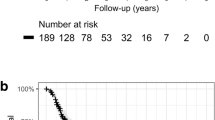

The median follow-up period was 44 months for all patients and 61 months for living patients. At 5 years, OS was 65%, PFS was 55%, and the cumulative incidence of LR was 15%. Figs. 1a, 2a and 3a show OS, PFS, and cumulative incidence of LR in all patients, operable patients, and medically inoperable patients. The OS, PFS, and cumulative incidence of LR did not differ between the operable patients and inoperable patients (Table 2). Figs. 1b, 2b and 3b show OS, PFS, and cumulative incidence of LR in patients treated with 48, 50, and 52 Gy. The 3- and 5-year data in these patients are shown in Table 3. The OS, PFS, and cumulative incidence of LR did not differ among the 3 groups. The 5-year OS was 69% for 57 stage IA patients and 53% for 14 stage IB patients (p = 0.44). The 5-year PFS was 55 and 54%, respectively (p = 0.98). The 5-year cumulative incidence of LR was 11 and 31%, respectively (p = 0.09).

a Cumulative incidences of local recurrence (LR) for all patients (solid line), operable patients (dashed line) and inoperable patients (dotted line). b Cumulative incidences of local recurrence for patients treated with 48 Gy/4 Fr (solid line), 50 Gy/4 Fr (dashed line), and 52 Gy/4 Fr (dotted line)

To evaluate efficacy of the newer protocol, we reanalyzed 113 patients enrolled in our first study at our own institution thereby updating the follow-up data. In the first study, the median follow-up period was 51 months for all patients and 73.5 months for living patients. At 5 years, OS was 53% in the first study, while it was 65% in the present study (p = 0.18). PFS was 44% vs 55% (p = 0.09), and the cumulative incidence of LR was 15% in both studies (p = 0.82). Although OS and PFS at 5 years and later tended to be higher in the second than in the first study, there were no differences. The curves for the second study tended to lie above (data not shown), and the lack of significance may be due to the patient number. If more patients are included in the second study, the differences may become significant. In this study, the OS, PFS, and cumulative incidence of LR did not differ between the operable and inoperable patients. So, the beneficial effect of SBRT especially in inoperable patients seems remarkable. Conventional radiotherapy yielded 5-year survival rates of 30% or lower in stage I NSCLC patients [26], so the advent of SBRT is quite valuable for these patients.

OS, PFS, and LR rates were also not greatly different between stage IA and stage IB patients. However, the LR rate for stage IB tended to be higher. If more patients are included, the differences may become significant. Nevertheless, improvement in treatment outcome may be relatively small, if any, even if we continue to use this second protocol. Improvement in local control is desirable for T2a tumors, and to achieve this, further dose escalation should be attempted. The use of more fraction numbers or particle therapy may be recommended [27, 28], but even when these policies are adopted, dose escalation should be investigated [29].